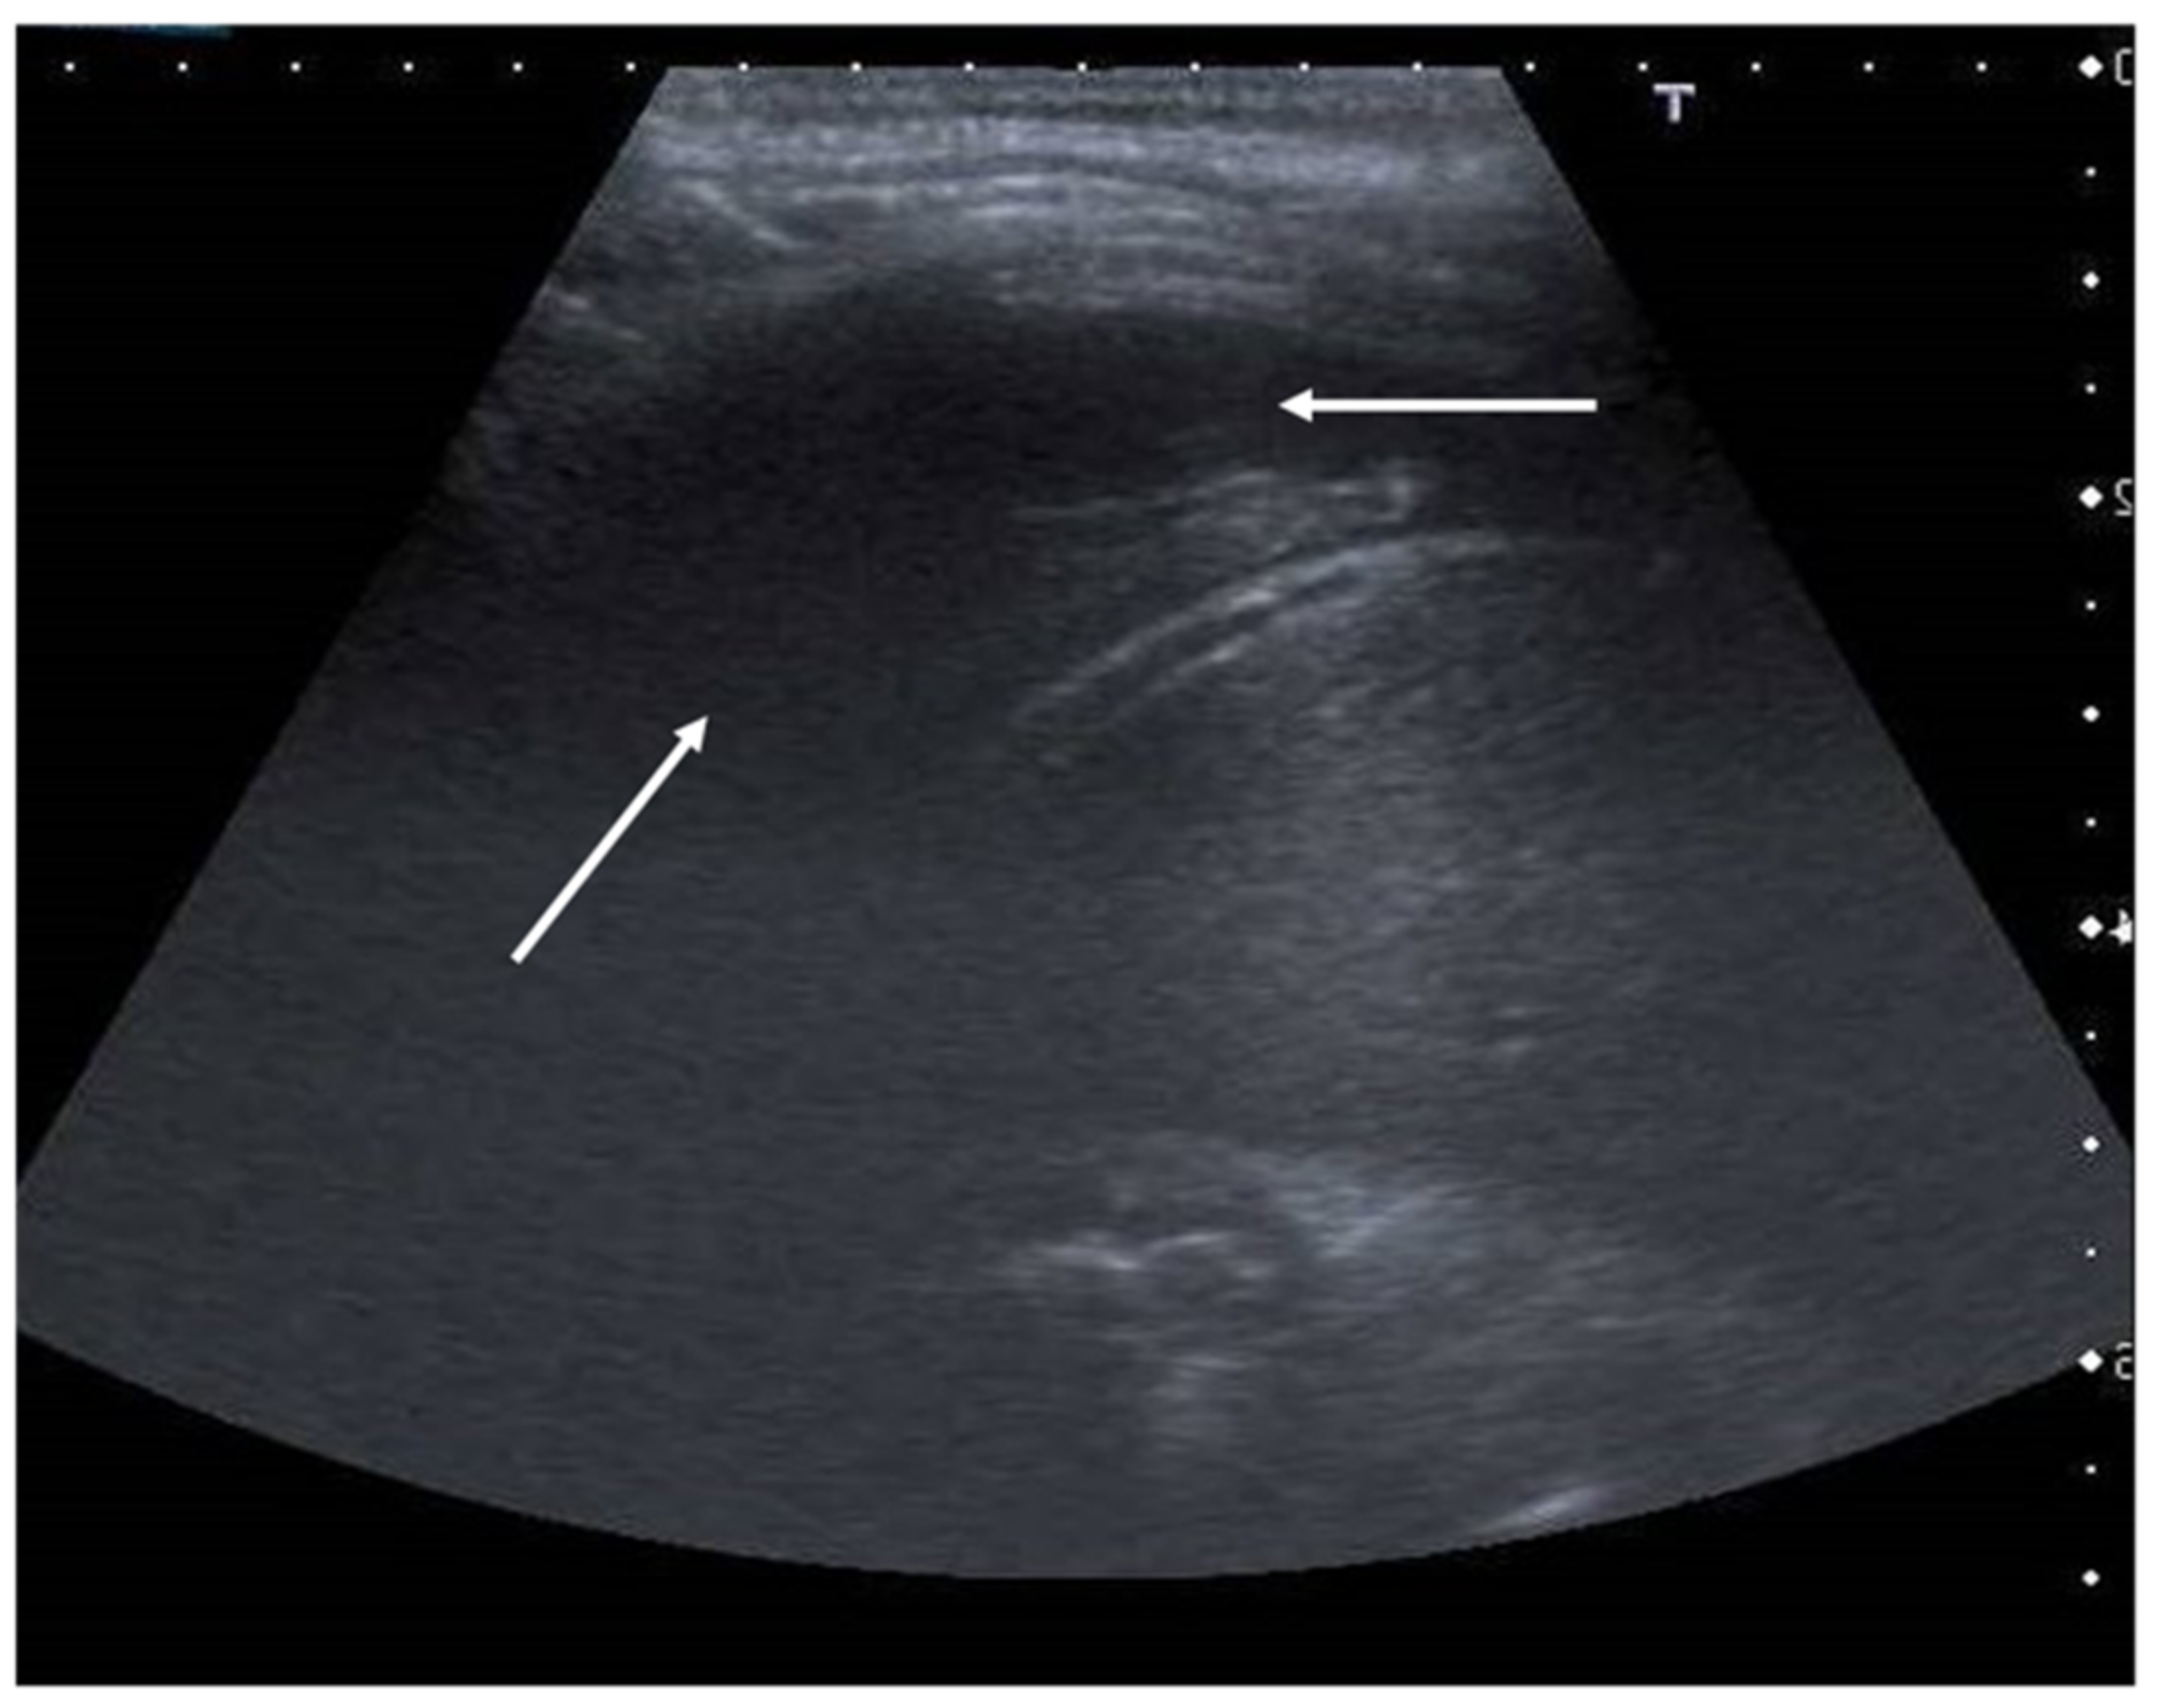

The role of LUS in identifying pleural effusion is also well established [53]. In fact, many studies have evaluated the efficacy of lung ultrasound in the diagnosis of pleural effusion, calculating its sensitivity and specificity, which have often been close to 100% [54]. These studies have confirmed the superiority of ultrasound over CXR in pleural effusion detection due to the capability of ultrasound to detect fluid collections as small as 20 mL [55]. Usually, pleural effusion can be visualized by ultrasound as a dark and anechogenic region located above the diaphragm that also determines the disappearance of the mirror image of the liver and spleen in the lung fields, which can be visualized in the healthy lung (Figure 10) [14]. Ultrasound also allows quantifying the amount of fluid accumulated in the pleural cavity well and characterizing the fluid collection differentiating a transudate from an exudate. The transudate is characterized by a dark image without internal echoes, representing an uncomplicated collection, while an image characterized by a septate or multiloculated corpuscular fluid collection is typical of the exudate [14].

Figure 10.

Anechogenic fluid collection above the diaphragm suggestive of pleural effusion (white arrows).